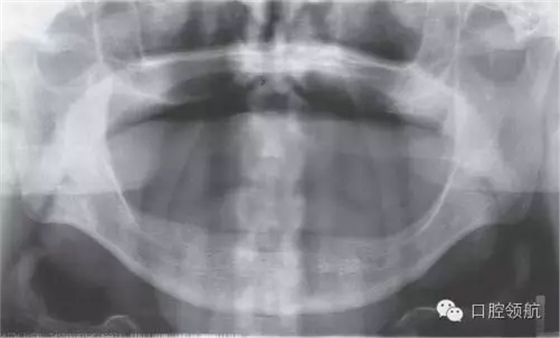

初診時(shí),口內(nèi)所見(圖1),曲面斷層片顯示(圖2),患者植入?yún)^(qū)骨量不足,前庭溝深度不足,附著齦的量不足。

圖2 初診時(shí)曲面斷層影像。